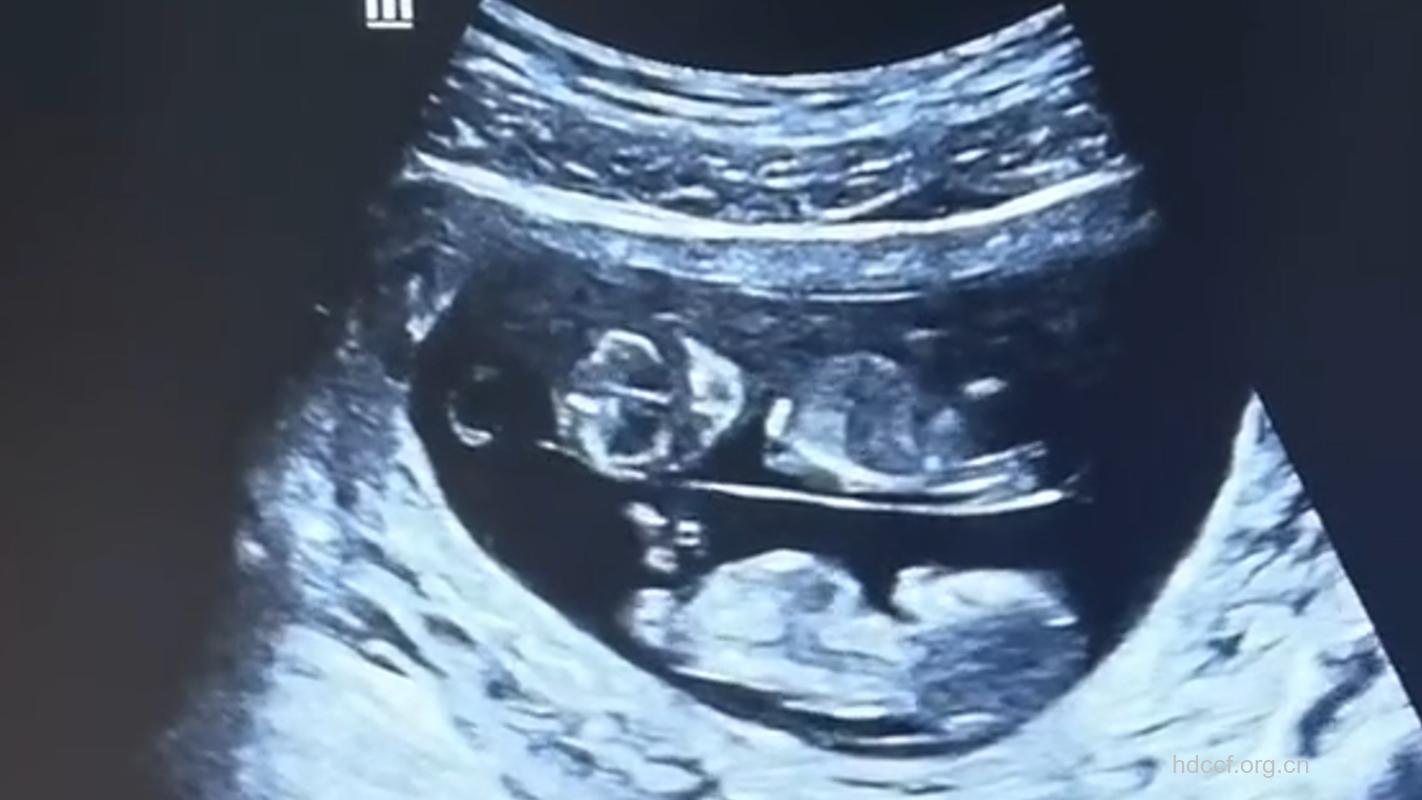

你的双胞胎在第8周已经长出能够弯曲的胳膊和腿,他们的心脏都咚咚咚地跳了两周了,宝宝脑子里的神经细胞正向外伸展,互相连接。

实际上,你可能已经为验证是否怀孕去医院做过检查了,那么这一次,同样非常关键。一般在确认怀孕后,在孕期第8周-12周时进行第一次产检,产前检查可以了解软产道及骨盆腔内的生殖器官有无异常,这样医生可以对你分娩的情况提早做估计。如果你打算从怀孕一直到分娩都定期去同一家医院检查,那么最好从一开始就慎重地进行选择。孕妇手册是全国通用的,每一次产前检查的结果,都必须详细记录在手册上面,这是提升产检品质的基本工作,如果医护人员忘记了,不妨提醒他们或主动加以要求。